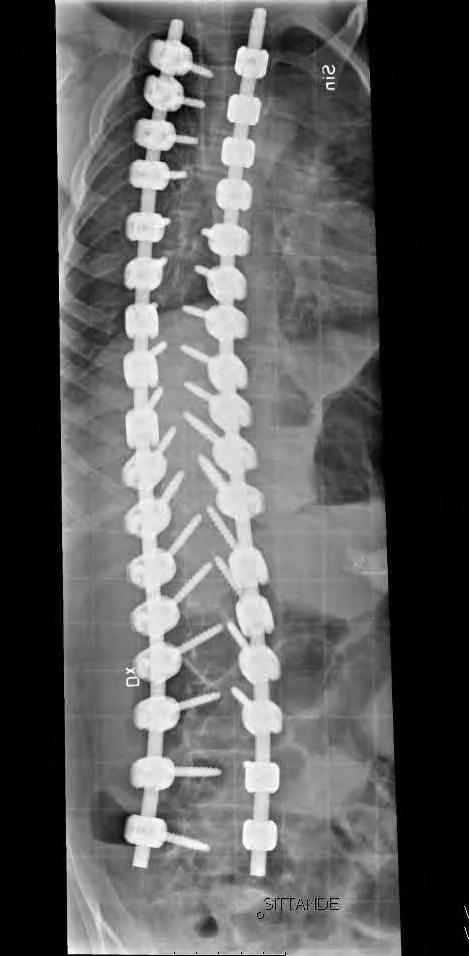

Operativ behandling

Vid operation för neuromuskulär skolios har man i allmänhet större blodförlust än vid idio-

11-årig flicka med CP och spastisk tetrapares. Hon hade en extremt snabb skoliosutveckling från Cobb 45 grader till drygt 70 grader på tre månader. detta föranledde en snar op från Th2 till L5 med transpedikulära skruvar enl. Suk. Blödningen uppgick till 1500 ml. Postoperativt har vi inga restriktioner avseende mobiliseringen då så många fixationspunkter användes. Patienten hade postoperativt lunginflammation som dock snabbt svarade på antibiotikabehandling.

patisk skolios varför preoperativ tappning för autolog transfusion bör övervägas. Korrektion och fusion är ofta indicerade då

Cobbvinkeln är 40 – 60 grader. Vid CP är en bakre operationsmetod idag den vanligaste. Traditionellt har man använt sublaminär stag-

fixation med cerclage, en utveckling som Luque i Mexico utvecklade i slutet av 1970-talet. Idag används allt oftare transpedikulära skruvar enligt Suk från Sydkorea. Ett ständigt debattämne är när man ska inkludera bäckenet i instrumenteringen. Ett snedställt bäcken över 20 grader brukar ofta anges som indikation för denna åtgärd. Bäckenet och dess ställning kan betraktas som en del av deformiteten som helhet och är linjen rak från L4 och ner till bäckenet kan man enligt egen erfarenhet ofta stanna vid L5 och förlita sig på den ofta utomordentligt väl utvecklade iliolumbala ligamentapparaten. Vid operationen brukar instrumenteringen sträcka sig från övre bröstryggen (Th 1 – Th 2) till L5 eller bäckenet. I de mest krökta delarna av ryggen gör man ofta multipla bakre lösningar. Det går till så att man gör fenestreringar intill epiduralrummet och resecerar intervertebrallederna. Vanligtvis sätter vi skruvar i samtliga tillgängliga pediklar för att fördela lasterna under själva korrektionen så man inte riskerar en tidig skruvlossning (pull out). I rigida fall använder vi oss av reduktionsskruvar som har en förlängning av skruvarnas gängor, man fördelar då krafterna till många skruvar under korrektionsfasen. När korrektionen är färdig biter man av skruvhuvudsförlängningarna. Stagtjockleken ska vara så stor som patientens konstitution tillåter, framförallt för att få en bättre korrektion men också för att minska risken för stagbrott. Ibland använder vi ett grövre stag på korrektionssidan, den konkava och djupare belägna sidan och ett med mindre diameter på den konvexa sidan där implantaten ligger mer ytligt.

12 årig flicka med CP. Hon hade fått en starkt försämrad sittställning på grund av progressiv lumbal skolios. vid opererationen användes bakre teknik för att först få korrektion av den lumbala skoliosen. Operationen extenderades ovan Th12 med tunnare stag som är längre än nödvändigt vid operationstillfället. Syftet var att man med denna konstruktion (Shilla-teknik) har stag som ska kunna glida i skruvhuvudena i bröstryggen, allt för att kunna få thorax att växa ytterligare. I thorakalryggen infördes skruvarna transmuskulärt med hjälp av navigationsutrustning för att inte stimulera till bakre fusion.

Preop PA sittande visar en 65-gradig skolios enligt Cobb.

Postop PA av ländrygg och nedre bröstrygg visande en god korrektion av skoliosen.

CT-lågdos med axialt snitt L3 preop visande 18 graders rotation enl. Aaro.

CT-lågdos med axialt i L3, postop visande reduktion av rotatione till 8 grader. Man ser också att kotkroppen ligger mer centralt i torson.

Lateral bild av övre delen av konstruktionen där de ”för långa” stagen syns väl.

Blodförlust under ingreppet var c:a 500 ml.

ma räcker och att naturen sköter fusionering själv när en rigid fixation väl uppnåtts.

Respiratoriska komplikationer vanliga

Respiratoriska komplikationer är vanliga i det postoperativa förloppet och incidenser är rapporterade från 10 till 20 procent. Tidiga och sena implantatassocierade infektioner är vanligare än vid operationer för idiopatisk skolios. Vidare ökar infektionsrisken då man engagerar bäckenet i fixationen.

Watanabe och medarbetare rapporterade 2009 i en retrospektiv serie av 84 patienter med spastisk CP att 92% av patienterna / föräldrarna överlag var positiva till utfallet av operationen; 93% fick en förbättrad sittfunktion och 94% rapporterade bättre kosmetik. I 79% av fallen skulle man rekommendera operationen till andra med neuromuskulär skolios.